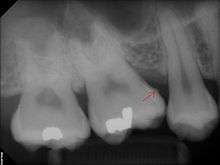

The processes of calculus formation from dental plaque are not well understood. Supragingival calculus formation is most abundant on the buccal (cheek) surfaces of the maxillary molars and on the lingual (tongue) surfaces of the mandibular incisors.[13] These areas experience high salivary flow because of their proximity to the parotid and sublingual salivary glands. Subgingival calculus forms below the gumline and is typically darkened in color by the presence of black-pigmented bacteria,[13] whose cells are coated in a layer of iron obtained from heme during gingival bleeding.[14] Dental calculus typically forms in incremental layers[15] that are easily visible using both electron microscopy and light microscopy.[7] These layers form during periodic calcification events of the dental plaque,[13] but the timing and triggers of these events are poorly understood. The formation of calculus varies widely among individuals and at different locations within the mouth. Many variables have been identified that influence the formation of dental calculus, including age, gender, ethnic background, diet, location in the oral cavity, oral hygiene, bacterial plaque composition, host genetics, access to professional dental care, physical disabilities, systemic diseases, tobacco use, and drugs and medications.[13]